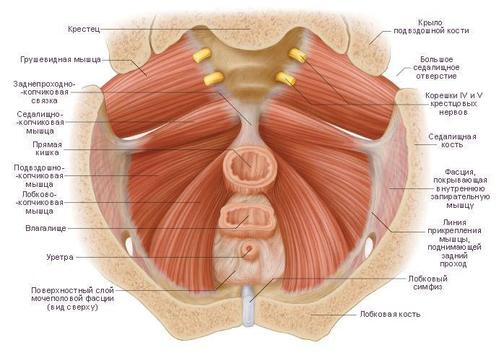

Гимнастика Кегеля для мужчин: упражнения для простаты